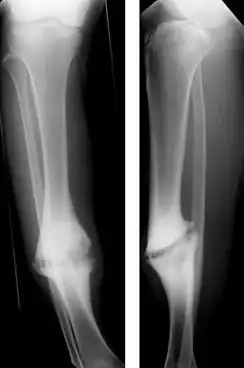

جوش نخوردگی ( به انگلیسی: Nonunion )، عدم التیام دائمی استخوان، پس از شکستگی است، مگر این که مداخله ای ( همچون جراحی ) صورت پذیرد. شکستگی همراه با جوش نخوردن، اغلب موجب شباهت ساختاری با مفصل رشته ای می گردد، و ازین رو به آن اغلب "مفصل کاذب" یا سودو - آرتروزیس ( به انگلیسی: pseudoarthrosis ) ( یا آرتروزیس کاذب ) گفته می شود ( از یونانی pseudo - به معنای کاذب، و arthrosis به معنای مفصل ). تشخیص عموماً هنگامی صورت می پذیرد که بین دو تصویربرداری پزشکی چون اشعه X یا CT اسکن، التیامی صورت نپذیرفته باشد. فاصله این دو تصویربرداری اغلب ۶ - ۸ ماه است.

از آنجا که فرایند التیام استخوان کاملاً متغیر است، جوش نخوردن ممکن است در موارد معدودی، بدون مداخله برطرف شده و ترمیم گردد. در کل، اگر جوش نخوردگی پس از گذر ۶ ماه از جراحت هنوز برقرار باشد، بدون درمان ویژه ارتوپدیک درمان نشده باقی خواهد ماند. جوش نخوردگی که پس از طی مدتی التیام یابد را "جوش نخوردگی تأخیری" می نامند.